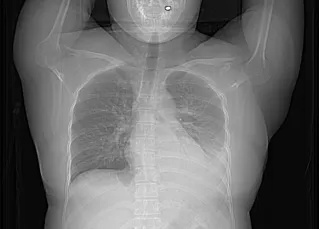

患者入院复查CTPA

患者影像检查变化